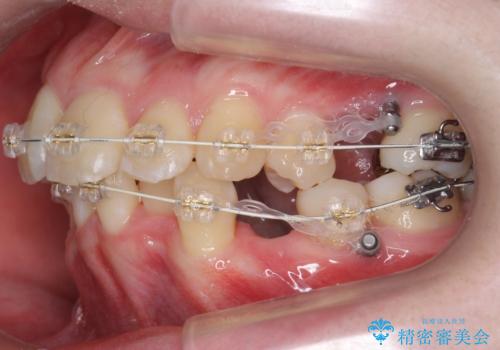

20代女性 前から5番目の歯を抜歯

- ワイヤー矯正

- 3年8ヶ月

- 前歯のがたつき、前突を主訴に来院。

通常前から4番目の歯を抜歯するのですが、左上5番の形が矮小であったため、そちらを抜歯しました。(患者様の希望にそっています。)

前から5番目の歯を抜くと、長くて1年ほど矯正期間が延長しますが、形に異常がない左上4番を抜かずに保存しています。